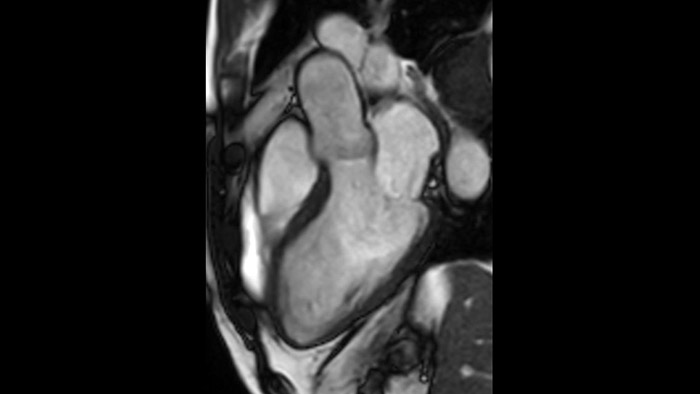

Diagnostic and prognostic utility of cardiac MR is increasing. Assess the anatomy and function of the heart using cine acquisitions, acquire information about perfusion and viability of the cardiac tissue, visualise potential edema with black blood sequence, access and even quantify tissue characterisation with CardiacQuant.

IntelliSpace Portal MR Caas5,6 4D Flow post-processing solution enables generation of 3D volume reconstructions, to visualise and evaluate blood flow in cardiovascular structures, including heart valves, chambers, and vessels, based on cardiovascular MR 4D Flow imaging.